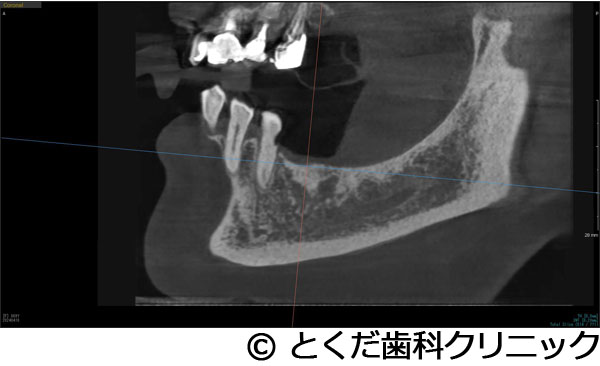

¡Ú¾ÉÎã4¡Ûº¸¾å4È֤ϥ¤¥ó¥×¥é¥ó¥ÈÈ´»õ¨»þËäÆþ¡¢º¸¾å6È֤Ͼå³Ü´û¸¹ü1¡Á2mm¤Î¥±¡¼¥¹¤Ç¥°¥é¥Õ¥È¥ì¥¹¥µ¥¤¥Ê¥¹¥ê¥Õ¥È¤ò»Ü¹Ô º¸²¼56¤Ï·ç»¤¬Â礤¯¡¢²¼³Ü¿À·Ð¤Þ¤Ç¤Îµ÷Î¥¤¬¤Ê¤¤¥±¡¼¥¹¤Ç¡¢²¼»õÁå´ÉËãáã¤ò²óÈò¤¹¤ë¤¿¤á¤Ë¥·¥ç¡¼¥È¥¤¥ó¥×¥é¥ó¥È¤ò»ÈÍÑ ºÇ½ªÊäÄÖʪ¤Ïº¸¾å456¤Î3¥æ¥Ë¥Ã¥È¤Î¥¸¥ë¥³¥Ë¥¢¥Ö¥ê¥Ã¥¸¡¢º¸²¼56¤Ï¥¸¥ë¥³¥Ë¥¢¤ÎÏ¢·ë´§¤òÁõÃ夷¤¿¥±¡¼¥¹

- º¸¾å4È֤ϥ¤¥ó¥×¥é¥ó¥ÈÈ´»õ¨»þËäÆþ¡¢º¸¾å6È֤Ͼå³Ü´û¸¹ü1¡Á2mm¤Î¥±¡¼¥¹¤Ç¥°¥é¥Õ¥È¥ì¥¹¥µ¥¤¥Ê¥¹¥ê¥Õ¥È¤ò»Ü¹Ô º¸²¼56¤Ï·ç»¤¬Â礤¯¡¢²¼³Ü¿À·Ð¤Þ¤Ç¤Îµ÷Î¥¤¬¤Ê¤¤¥±¡¼¥¹¤Ç¡¢²¼»õÁå´ÉËãáã¤ò²óÈò¤¹¤ë¤¿¤á¤Ë¥·¥ç¡¼¥È¥¤¥ó¥×¥é¥ó¥È¤ò»ÈÍÑ ºÇ½ªÊäÄÖʪ¤Ïº¸¾å456¤Î3¥æ¥Ë¥Ã¥È¤Î¥¸¥ë¥³¥Ë¥¢¥Ö¥ê¥Ã¥¸¡¢º¸²¼56¤Ï¥¸¥ë¥³¥Ë¥¢¤ÎÏ¢·ë´§¤òÁõÃ夷¤¿¥±¡¼¥¹

¼£ÎÅÊýË¡

´µ¼ÔÍͤϺ¸¾å¤ÎưÍɤ¬º¸¾å56¤ÎÈ´»õ¤ò´õ˾¡£¤½¤Î¸å¡¢¥¤¥ó¥×¥é¥ó¥È¼£ÎŤò´õ˾¤·¤¿¤¿¤áº¸¾å4¤Ë´Ø¤·¤Æ¤ÏÈ´»õ¨»þËäÆþ¡£º¸¾å6¤Ë´Ø¤·¤Æ¤Ï¡¢´û¸¹ü1¡Á2mm¤Ç¥¤¥ó¥×¥é¥ó¥È¼£ÎŤ¬¸·¤·¤¤¾õÂ֤Ǥ¢¤Ã¤¿¤¬¡¢¥°¥é¥Õ¥È¥ì¥¹¥µ¥¤¥Ê¥¹¥ê¥Õ¥È¤Ç¥¤¥ó¥×¥é¥ó¥ÈËäÆþ¤ò¹Ô¤¤¤Þ¤·¤¿¡£¤½¤Î¸å¡¢2¥õ·îȾ¸å¡¢ÂçÉý¤Ë¹ü¤¬·ç»¤·¤Æ¤¤¤ë²¼³Ü56¤ËÂФ·¤Æ¥·¥ç¡¼¥È¥¤¥ó¥×¥é¥ó¥È¤ò»ÈÍѤ·¤Æ¡¢²¼³Ü¿À·Ð¤Î»½ý¤òÈò¤±¤Æ¥¤¥ó¥×¥é¥ó¥ÈËäÆþ¤Î¼ê½Ñ¤ò½ª¤¨¤Æ¤¤¤Þ¤¹¡£¤½¤Î¸å2¥õ·î¸å¤Ë¸÷³Ø°õ¾Ý¤Ç°õ¾Ý¤ò¹Ô¤¤¡¢º¸¾å456¤Ï3¥æ¥Ë¥Ã¥È¤Î¥¸¥ë¥³¥Ë¥¢¥Ö¥ê¥Ã¥¸¤òÁõÃå¡£²¼º¸56¤Ë´Ø¤·¤Æ¤Ï¹ü·ç»¤¬Â礤¤¤¿¤á¡¢»õ´§Ä¹¤¬¤À¤¤¤ÖŤ¯¤Ê¤ë¤¿¤á¡¢¥¸¥ë¥³¥Ë¥¢¤ÎÏ¢·ë´§¤òÁõÃ夷¤Æ¼£ÎŤò½ª¤¨¤Æ¤¤¤Þ¤¹¡£

¾å³Ü6¤Ë´Ø¤·¤Æ¤Ï´û¸¹ü¤¬¾¯¤Ê¤¯¡¢¸·¤·¤¤¼£ÎŤǤϤ¢¤ê¤Þ¤·¤¿¤¬¡¢5¥õ·î¤Ç¼£ÎŤò½ª¤¨¡¢´µ¼ÔÍͤοÈÂÎŪ¡¢»þ´ÖŪ¡¢ÈñÍÑŪÉéô¤òºÇ¾®¸Â¤ËÍÞ¤¨¤ë¤³¤È¤¬¤Ç¤¤¿¤È¹Í¤¨¤Þ¤¹¡ÊÄ̾ï¤À¤È¼£ÎŤ¬ÉÔ²Äǽ¤È¸À¤ï¤ì¤ë¤³¤È¤¬Â¿¤¤¥±¡¼¥¹¤À¤È¹Í¤¨¤Þ¤¹¡£¤Ç¤¤¿¾ì¹ç¤â¡¢½¾Íè¤Î¥µ¥¤¥Ê¥¹¥ê¥Õ¥È¤ò¹Ô¤¤¡¢1ǯ°Ê¾å¤«1Ç¯ÄøÅ٤μ£ÎÅ´ü´Ö¤¬¤«¤«¤ë¤«¡¢»þ´ÖŪ¤ä¿ÈÂÎŪ¤Ë¤â¡¢¤Þ¤¿¡¢ÈñÍÑÌ̤ˤª¤¤¤Æ¤â¡¢´µ¼ÔÍͤËÉéô¤ò¤«¤±¤ë¥±¡¼¥¹¤À¤È¹Í¤¨¤Þ¤¹¡Ë¡£¤Þ¤¿¡¢²¼³Ü¤Ï¹ü·ç»¤¬Â礤¯¡¢²¼»õÁå´É¤Ø¤Î±Æ¶Á¤¬¹Í¤¨¤é¤ì¤ë¥ê¥¹¥¯¤¬¹Í¤¨¤é¤ì¤ë¥±¡¼¥¹¤Ç¤·¤¿¤¬¡¢¥·¥ç¡¼¥È¥¤¥ó¥×¥é¥ó¥È¤ò»ÈÍѤ¹¤ë¤³¤È¤Ç°ÂÁ´¤Ë¼£ÎŤò½ª¤¨¤ë¤³¤È¤¬¤Ç¤¤Þ¤·¤¿¡£